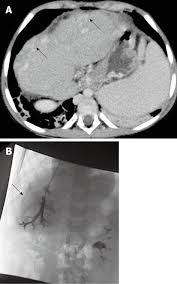

This case presents the classic sonographic findings of biliary atresia, including: It is the most common cause of. Imaging features on preoperative ultrasonography (us) and magnetic resonance imaging (mri) were compared between the cba and cc. Ba is not associated with calculi, neoplasm, or rupture. Biliary atresia is a rare condition in newborn infants in which the common bile duct between the liver and the small intestine is blocked or absent.

On the left we see the normal development of the ductal plate. Divided into fetal / embryonic and perinatal / acquired forms (emedicine: Imaging features on preoperative ultrasonography (us) and magnetic resonance imaging (mri) were compared between the cba and cc. This study compared clinical and radiologic differences between cystic biliary atresia (cba) and choledochal cyst (cc) type ia/b. It is the most common cause of. Hepatocellular cholestasis results from impairment of bile formation and indicates defective functioning of most or all hepatocytes. The body needs bile to aid digestion and carry wastes from the liver out of the body. It is one of the most common causes of neonatal cholestasis, often causing cirrhosis immediately and leading to death and accounts for over half of children who undergo liver transplantation. Increased echogenicity along the anterior. Biliary atresia, also known as extrahepatic ductopenia and progressive obliterative cholangiopathy, is a childhood disease of the liver in which one or more bile ducts are abnormally narrow, blocked, or absent. The diagnosis of biliary atresia could be made with mrc (fig 1b). Biliary atresia imaging accessed 26 october 2017) fetal / embryonic form: Color doppler us findings in neonates and infants by lee and colleagues (1) in the july 2009 issue of radiology.

Imaging features on preoperative ultrasonography (us) and magnetic resonance imaging (mri) were compared between the cba and cc. Über 7 millionen englischsprachige bücher. Gallbladder length less than 19 mm is suggestive for atretic gallbladder 2. On the left we see the normal development of the ductal plate. Left untreated or with failure of the kasai procedure, biliary atresia progresses towards … Unequivocal evidence of intestinal excretion of radiolabel confirms patency of the extrahepatic biliary system. Based on the results of our series, the size of the gallbladder does not seem to be a decisive finding for the diagnosis of biliary atresia. It is one of the most common causes of neonatal cholestasis, often causing cirrhosis immediately and leading to death and accounts for over half of children who undergo liver transplantation. Symptoms start shortly after birth; When blocked ducts prevent bile from being excreted, the liver becomes damaged. Hepatocellular cholestasis results from impairment of bile formation and indicates defective functioning of most or all hepatocytes. Congenital absence of biliary tree us: Postoperative biliary tract (i.e., biliary leak) !